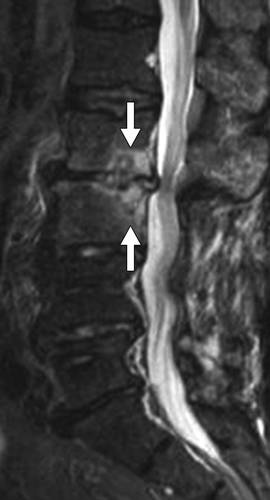

![]()

图14B--椎体中线水平的矢状T1加权未增强MR图像显示,从背侧压缩椎管的低信号包裹性积液(箭头)。